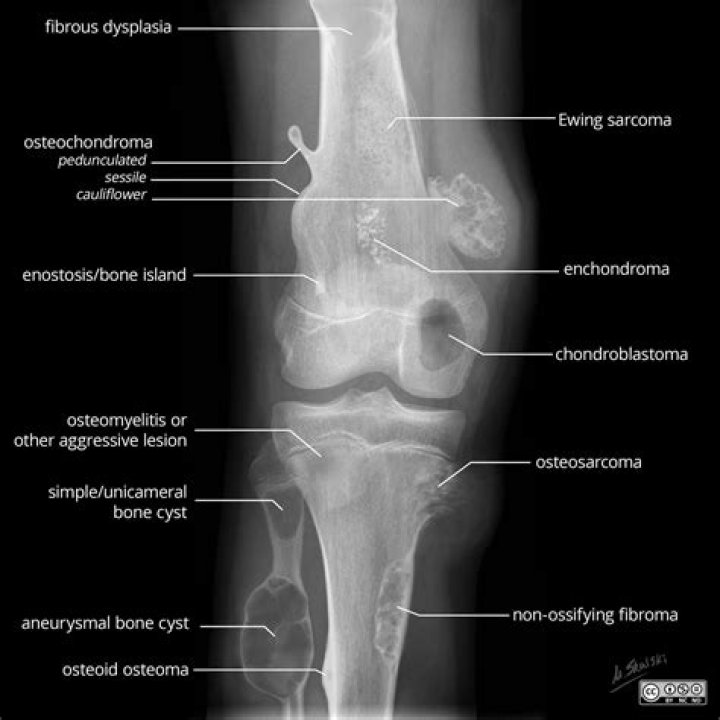

Although it is rare for an osteochondroma to change into a cancerous tumor, it is possible. In adults, a thick covering of cartilage over the tumor is one